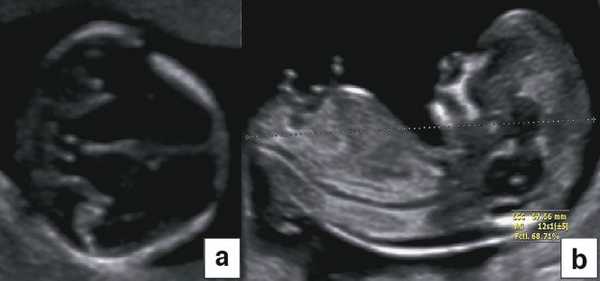

Некоторые ультразвуковые измерения в I триместре обязательны для выполнения. В большинстве случаев гестационный возраст до 15 нед с определенной степенью точности оценивают по показателям бипариетального размера (БПР) и копчико-теменного размера (КТР) (рис. 1). В дальнейшем эту информацию дополнять не будут, а использовать будут в основном для установления задержки внутриутробного развития, при планировании обследования по поводу врожденных аномалий и послеродовых осложнений. УЗИ на сроках между 11 нед 0 дней и 13 нед 6 дней необходимо постоянно сравнивать с данными обследования на сроках между 7 и 10 нед. Таким образом, УЗИ в I триместре должно помочь обнаружить ряд аномалий развития плода, например триплоидию [1].

В начале 90-х годов прошлого века в практику был внедрен метод измерения толщины воротникового пространства (ТВП) в I триместре беременности, и к настоящему времени его считают показателем не только анеуплоидии, но и широкого спектра наследственных синдромов и пороков развития [2]. K. Николаидес (K. Nicolaides) с группой исследователей предложили новую модель скрининга на анеуплоидию и установили правила использования этого метода, в частности необходимость применения кривой обучения, проведения аудита, качественного (процедура оценки качества изображений) и количественного (медиана, дельты-ТВП и т.д.). Фонд медицины плода (Fetal Medicine Foundation) стандартизировал предложенный ими клинический протокол и установил правила сертификации для повышения качества медицинской помощи и уменьшения изменчивости результатов данных скрининга [3, 4]. Измерение ТВП можно проводить вручную (рис. 2a) или полуавтоматически (рис. 2b), чтобы результаты измерений были более воспроизводимыми. Кроме того, компания Samsung разработала дополнительный метод измерения показателей ТВП - 5D NT, позволяющий точно выявить срединно-сагиттальную плоскость и улучшить оценки по шкале Германа (Herman score).

Диагноз хориальности и количества амнионов

УЗИ при двойне в основном должно выявить хориальность (ди- или монохориальность) и для монохориальных беременностей (моно- или диамниотических) - количество амнионов. При многоплодной беременности эта информация необходима для соответствующего ведения дискордантной мальформации, замедления роста, внутриутробной гибели плода или получения образцов ткани плода. Точность этой диагностики в течение I триместра может достигать 100%, а затем на протяжении беременности она уменьшается [7]. Дихориальность подтверждают выявлением лямбда-признака (рис. 4a). Наоборот, монохориальность диагностируют при отсутствии визуализации лямбда-признака или выявлении T-признака (рис. 4b) в межамниотической мембране, расположенной перпендикулярно хорионической пластине.

Рис. 4. Диагностика хориальности и количества амнионов в I триместре путем оценки лямбда-признака (a) и T-признака (b).